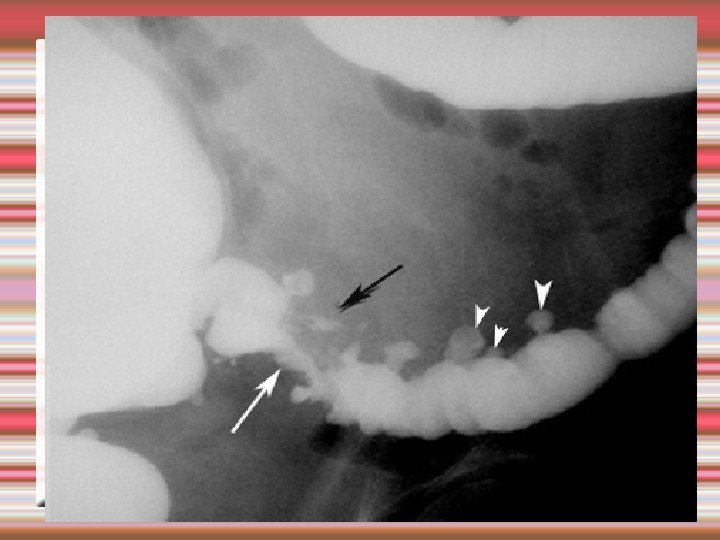

Диагностика дивертикулеза толстой кишки Жалобы и анамнез Ирригоскопия Фиброколоноскопия

Ирригография дивертикулез толстой кишки